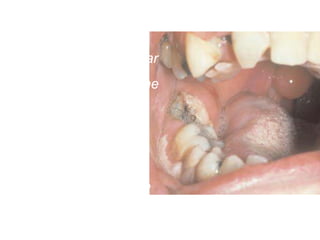

Buccal Space infection

•Canine Space infection •ClinicalPresentation. This is characterized : edema localized in the infraorbital region, • obliteration of the nasolabial fold and somewhat of the mucolabial fold. •the skin becomes taut and shiny due to suppuration, while its color is reddish

• #112 which spreads towards the medial canthus of the eye, lower eyelid, and side of the nose as far as the corner of the mouth. The edema at the infraorbital region is painful during palpation, and later on